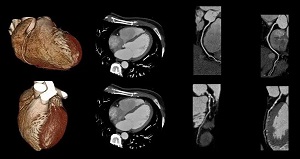

تشخیص بیماری های قلبی و عروقی

دکتر آزاده داودیان متخصص قلب وعروق دارای بورد تخصصی و فارغ التحصیل دانشگاه علوم پزشکی اصفهان می باشند.

Dr. Davodian's cardiology clinic in Borujen provides the following medical services:

Echocardiography, ECG interpretation, pre-surgery consultation, pregnant women's heart health consultation, high blood pressure diagnosis and treatment